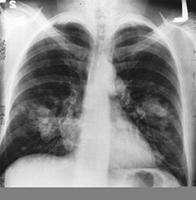

En el XII Congreso de la Sociedad Española de Oncología Médica (SEOM) que se celebra en Barcelona del 21 al 23 de octubre, se han presentado un número importante de comunicaciones sobre cáncer de pulmón que constatan avances en esta patología. Entre otros descubrimientos, el grupo Español de Cáncer de Pulmón (GEPC) ha demostrado que los tratamientos de cáncer de pulmón tienen una eficacia diferente si la persona afectada tiene determinadas alteraciones genéticas.

El Grupo Español de Cáncer de Pulmón (GECP) ha demostrado que los pacientes de cáncer de pulmón no microcítico (CPNM) con una mutación del gen EGFR podrán recibir tratamiento oral en vez de quimioterapia convencional, con un incremento de supervivencia en pacientes con estadios avanzados de cáncer. Por su parte, otro estudio español confirma que el cáncer de pulmón presenta características diferenciales en mujeres.

Desde abril de 2005 hasta noviembre de 2008, el GECP ha realizado un análisis prospectivo en 129 hospitales españoles de 2105 muestras de tumor de pacientes con cáncer de pulmón no microcítico avanzado en un laboratorio central para la determinación de mutaciones de EGFR, registrándose estos pacientes en una base de datos. Los pacientes que presentaban la mutación fueron 350 casos.